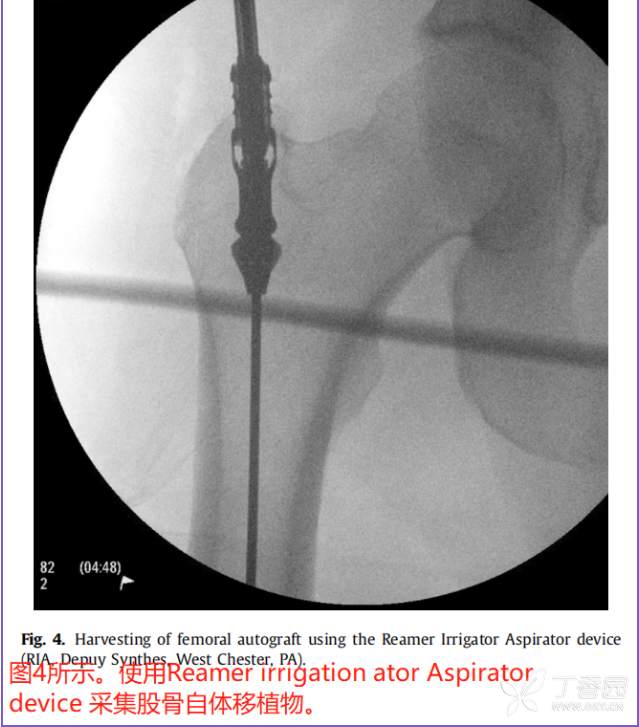

最近,国外采用Reamer灌洗吸引器系统(RIA, Depuy Synthes, West Chester, PA)从股骨髓腔进行扩孔已经成为一种常见的松质移植物来源。

在一项尸体研究中【3】,Finnan等人得出结论:无论是转子、“梨状窝”,还是逆行钻孔,用RIA扩孔后股骨的机械强度仍足以允许无支撑的单腿负重。但从另外一个尸体研究表明,这一过程仍然会有骨折风险,说明这是一个潜在的并发症。【4】

在一些研究中,RIA技术的结果与更传统的髂骨移植进行了比较。Belthur等报道使用RIA后愈合率为90%,而髂骨移植后愈合率为80%。【5】此外,在本研究中,RIA组的疼痛评分较低,但髂嵴骨移植物摘除术后并发症发生率较高。